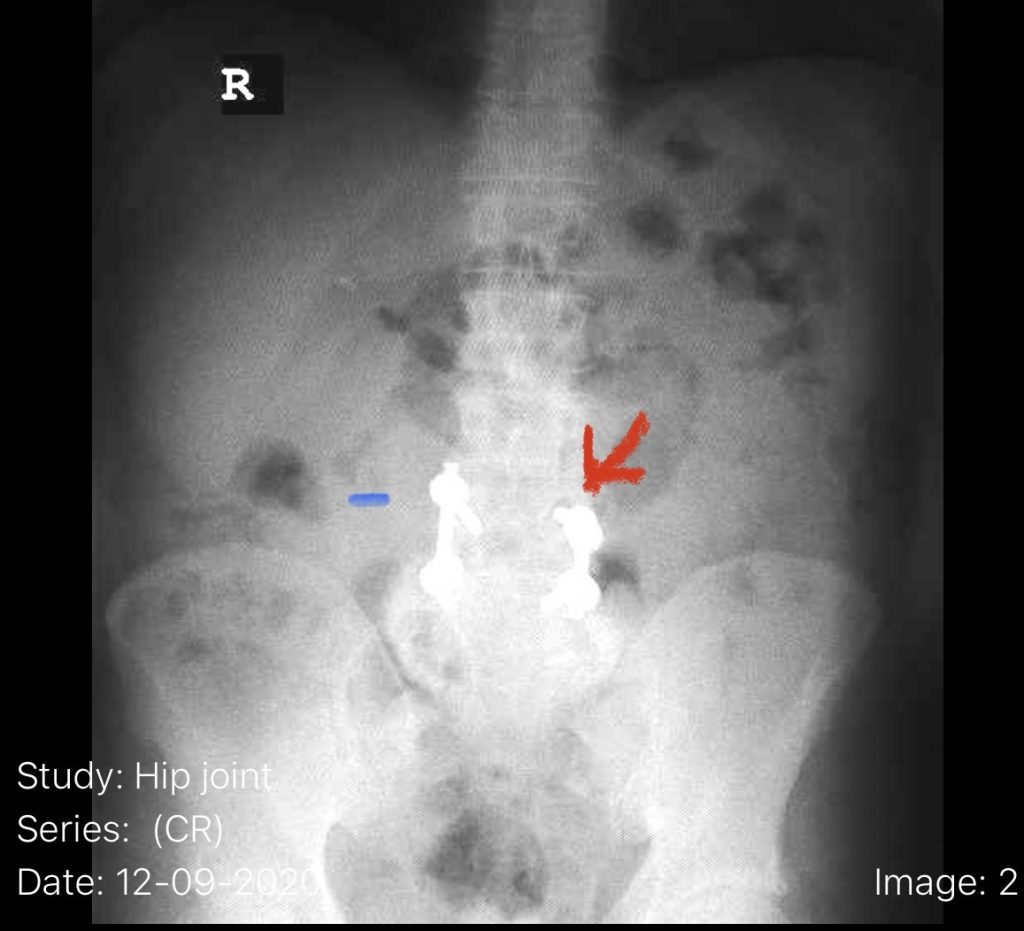

Fig 6: Plain AP x-ray demonstrating a lucency around the L4 screw (red arrow). Note the paucity of bone at the L4-5 level (blue dash) compared to below at L5.

The patient also had a retrolisthesis at L3-4 with mild stenosis. It was also noted that he had lucencies around the L4 screws, suggesting a pseudoarthrosis at L4-5. which is a lack of bony fusion (Fig 6). Patient was had failed conservative management and was taken to the operating room where his construct was explored. There was a complete lack of bony fusion mass between L4 and L5 and the screws were loose. Interestingly the L5-S1 region had a solid bony fusion where we had used BMP, but the L4-5 region did not. We removed the construct and removed the remnant of L4 lamina and the inferior processes and decompressed from L3 to to L5, decompressing well the L4 and L5 nerve roots. We placed new instrumentation from L3-5 with the use of BMP which was discussed with the patient prior to surgery (Fig 7). We also felt it was necessary because of the failure of the fusion. Post operatively the patient had an uneventful course with significant improvement of his prior symptoms.

Fig 7: Intraoperative fluoroscopic AP image of the new construct from L3-5. Note the very large lucency around prior L4 screw